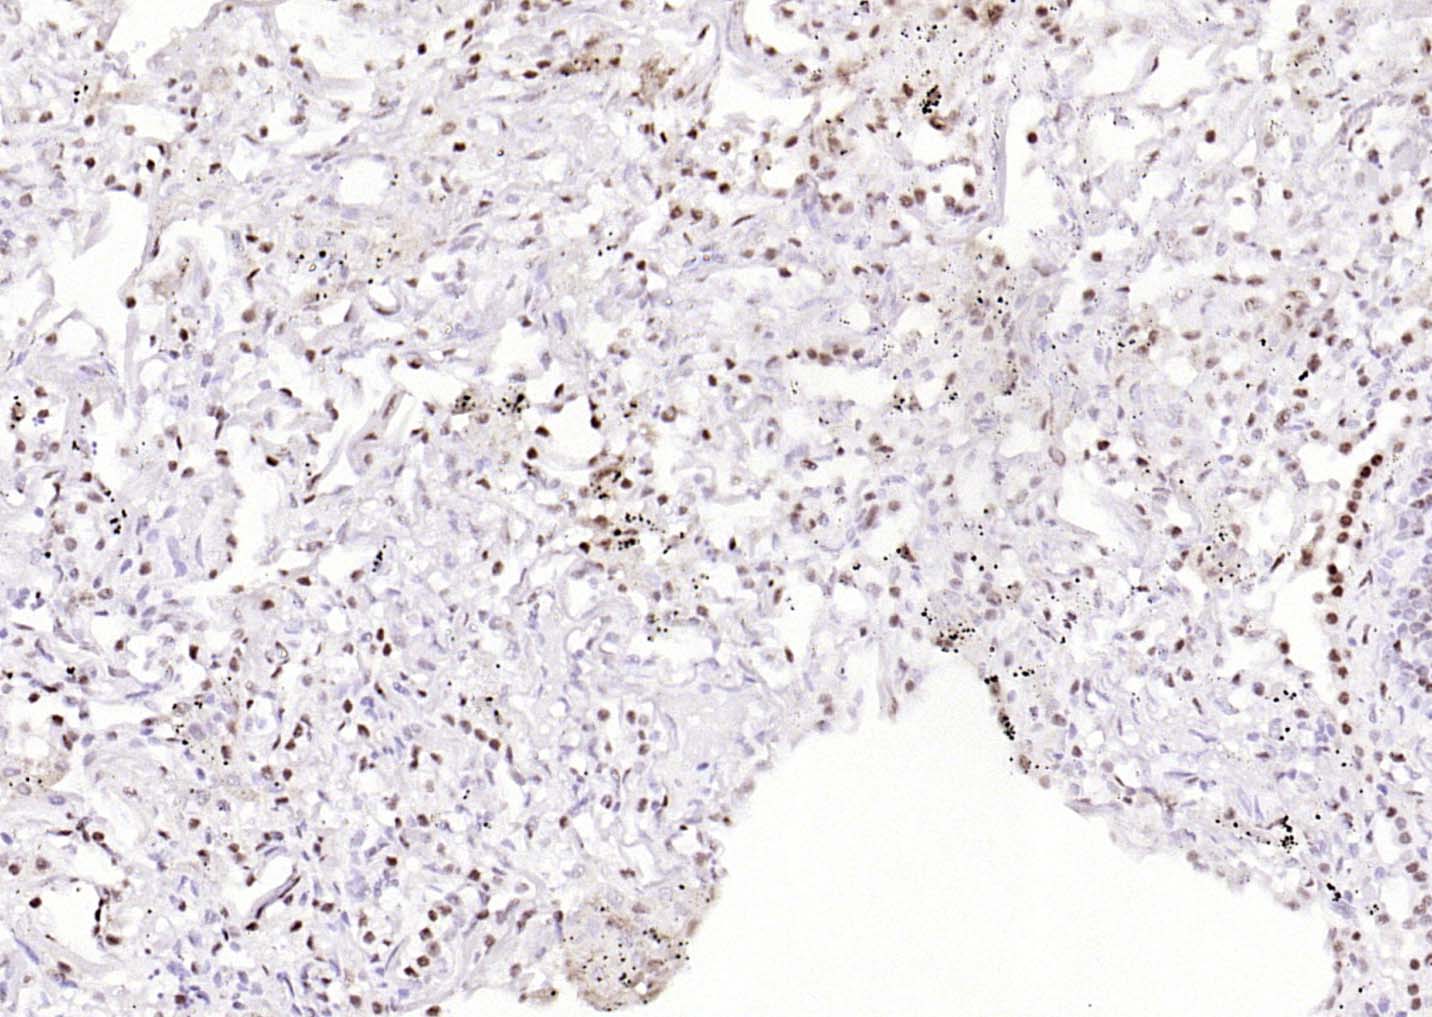

Paraformaldehyde-fixed, paraffin embedded (human breast carcinoma); Antigen retrieval by boiling in sodium citrate buffer (pH6.0) for 15min; Block endogenous peroxidase by 3% hydrogen peroxide for 20 minutes; Blocking buffer (normal goat serum) at 37°C for 30min; Antibody incubation with (phospho-ATF2 (Thr71)) Monoclonal Antibody, Unconjugated (bsm-52134R) at 1:200 overnight at 4°C, followed by operating according to SP Kit(Rabbit) (sp-0023) instructionsand DAB staining.